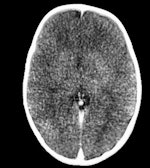

M. Gorincour a fait valoir que, passé un certain délai, tous les cadavres présentaient des traces d'embolie gazeuse, auparavant considérée comme une signature de la cause de décès chez les plongeurs ayant subi des changements de pression rapides. Il a indiqué que cette conclusion pouvait seulement être formulée si l'examen intervenait trois heures après l'accident, et impossible passé six heures.

Il a également découvert que l'emphysème sous-cutané, soit la présence d'air dans les tissus sous-cutanés, pouvait être provoqué par les efforts mis en œuvre pour ressusciter une victime de noyade, sans pouvoir être toujours attribuable à un accident.